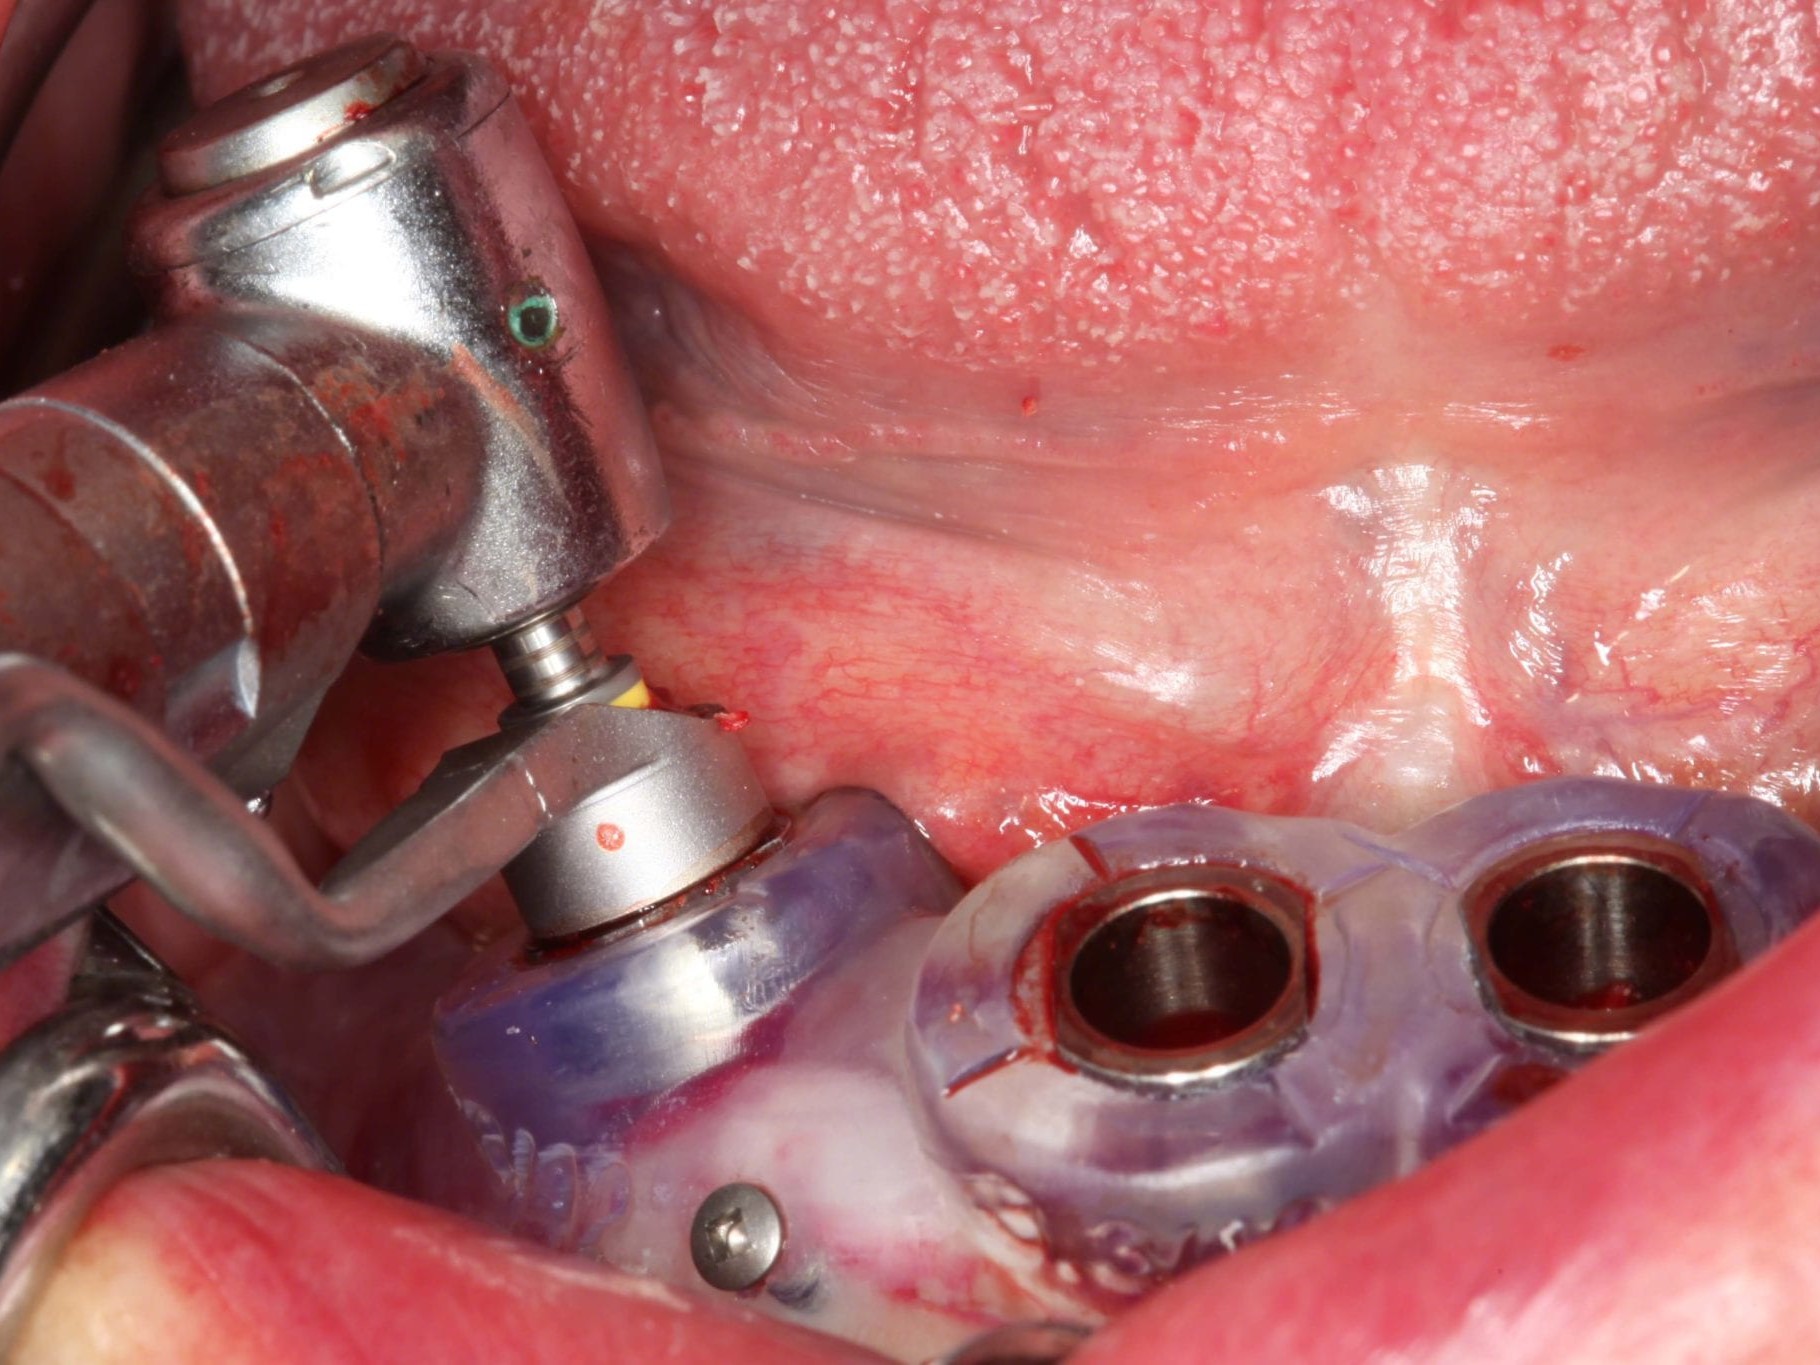

In Lokalanästhesie unter anästhesiologischem Standby mit intravenöser Antibiose mittels Clindamycin 600 mg 2mal/d wurde die Bohrschablone eingesetzt und mit Osteosyntheseschrauben fixiert (Abb. 8). Der Eingriff erfolgte nahezu flapless und somit transgingival. Nun erfolgte die Umsetzung des Straumann Hülse-in-Hülse-Konzeptes. Der Zylinder des Bohrlöffels wird in die an der Bohrschablone fixierten Hülse (Ø 5 mm) in den geplanten Regionen eingeführt. Für jeden Bohrerdurchmesser (Ø 2,2 mm und Ø 2,8 mm) ist ein entsprechender Bohrlöffel erhältlich. Jeder Bohrlöffel besitzt an seinen Enden Zylinder unterschiedlicher Höhe, die entsprechend chirurgischem Protokoll angewendet werden. Es wurden sämtliche Bohrstollen protokollgemäß aufbereitet (Abb. 9-11). Nach der Aufbereitung der Bohrstollen für die angulierten Implantate (Abb. 12-14) wurden die Straumann Bone Level Tapered Implantate (ø 3,3 mm) in regio 035 (Länge 10 mm) und 045 (Länge 12) gesetzt (Abb. 15). Abschließend wurden sämtliche Endpositionen der Implantate in regio 035 und 045 anhand der Lasermarkierungen am Übertragungsteil betreffend ihrer orovestibulären Ausrichtung exakt überprüft (Abb. 16). Nach Entfernung der Einbringhilfen und der Osteosyntheseschrauben konnte die Bohrschablone wieder entnommen werden. In regio 032 und 042 wurden nun die durchmesserreduzierten Straumann NNC (ø 3,3 mm Länge 12 mm) Implantate inseriert (Abb. 17, 18). Bei diesen Implantaten bedurfte es keiner Ausrichtung bezogen auf die orofasziale Ausrichtung. Hier musste die Insertionstiefe bezogen auf das NNC-Implantat beachtet werden (Abb. 19). Die NNC-Implantate wurden mit den entsprechenden Klebebasen versehen (Abb. 20). Danach wurden in regio 035 und 045 auf die Pro Arch Sekundärteile die dazugehörigen Retentionskappen (Abb. 21), die zur Vergrößerung der Oberfläche mit 120 μ Aluminiumoxyd abgestrahlt wurden, eingesetzt. Es erfolgte der typische Naht-Wund-Verschluss mit Einzelknopfnähten. Zum Abschluss erfolgte das prothetische Procedere mit der Eingliederung des Interimszahnersatzes in Okklusion (Abb. 22). Hierfür wurden die Retentionskappen und die Klebebasen mit dem Sofortprovisorium über ein selbsthärtendes fluoreszierendes kaltpolymerisierendes Paste-Paste-Kartuschensystem fixiert, dieser Zahnersatz extraoral versäubert (Abb. 23) und in der Mundhöhle refixiert (Abb. 24). Die Schraubenkanäle wurden mit Kunststoff verschlossen (Abb. 25). Abschließend erfolgte die radiologische Kontrolluntersuchung (Abb. 26).